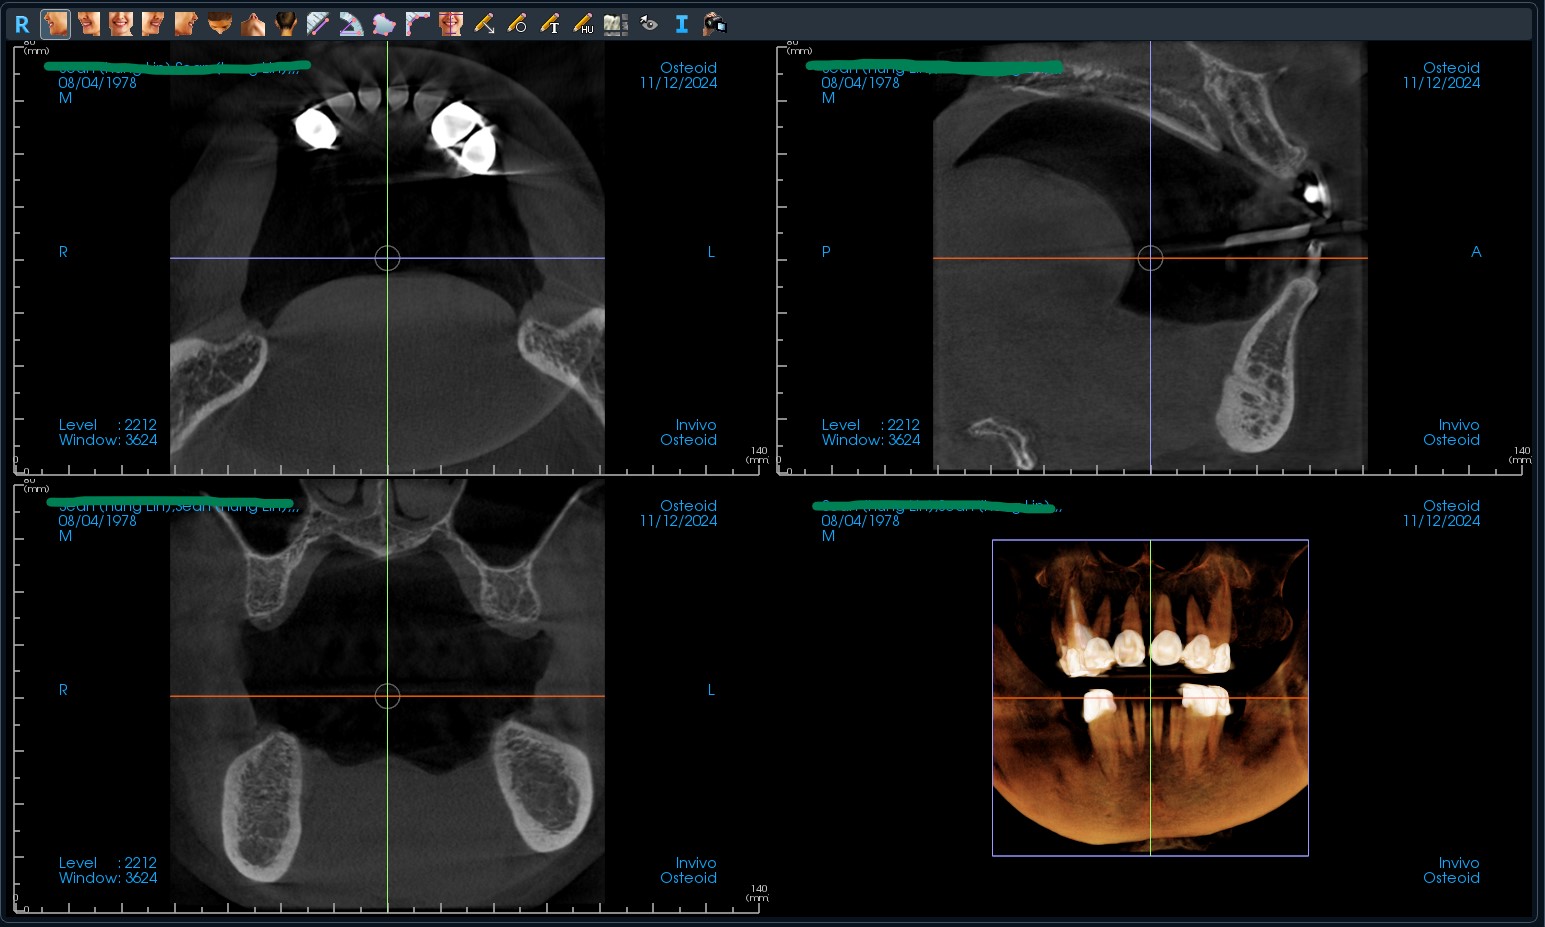

1.1. Dữ liệu cấu trúc xương (File DICOM)

Được xuất ra từ phim chụp CT Cone Beam (CBCT).

• Yêu cầu: * Trường nhìn (FOV) vừa đủ, bao phủ được vùng răng cần cấy ghép và các răng kế cận để làm điểm tựa.

• Bệnh nhân cần há miệng nhẹ (cách ly hai hàm) để tránh nhiễu ảnh tại mặt nhai.

• Định dạng: Đầy đủ các file trong thư mục DICOM (không nén thành file video hay ảnh đơn).

ct